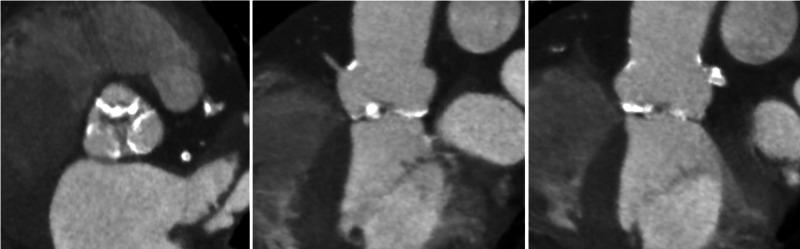

Transcutaneous aortic valve replacement (TAVR) has become a widely accepted minimally invasive approach for treatment of severe aortic stenosis. Self-expandable prostheses are commonly the device of choice, with excellent procedural success and durability. However, there have been several recent case reports of infolding of the self-expandable prosthesis during development with subsequent malfunction and need for further intervention. We present a case of self-expandable valve prosthesis infolding managed by balloon postdilation, and summarize the cases reported in the literature to date in an attempt to increase awareness of this serious technical problem and the factors associated with it.